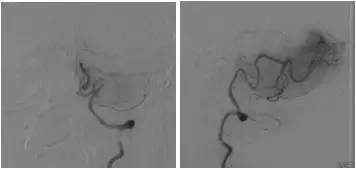

全麻下右股动脉穿刺置入6F动脉鞘,将6F导引导管至右椎动脉V1段,造影:右椎动脉V2段近段及远段狭窄。右椎动脉V4闭塞,右椎动脉V4远段经由脊髓前动脉代偿显影,左椎动脉由对侧椎动脉肌支及脊髓前代偿部分显影(图8)。

图8

路径图下沿导引导管送入Echelon-10微导管携带Pilot 50(0.014” ,190cm)微导丝,通过右侧椎动脉V4闭塞段,撤出微导丝微量造影证实微导管位于闭塞远端正常管腔(图9)。

图9